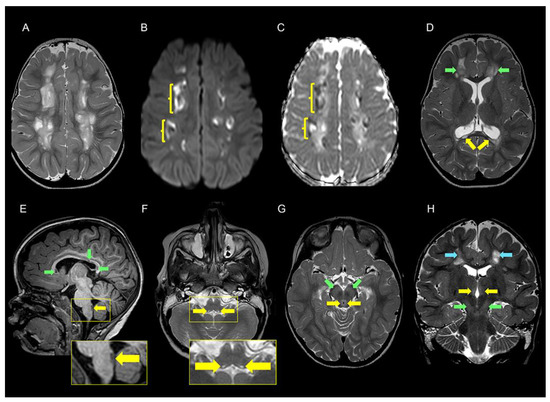

| Cerebral MRI | ||

| Cerebral hemispheres | Leukoencephalopathy, widespread with multiple cavities 3 | Scattered signal changes in deep white matter |

| Corpus callosum | Atrophy, multiple cysts 4 | Not reported |

| Brain stem and mesencephalon | Signal changes in pons and medulla oblongata 5 and periaqueductal grey matter 6 | Signal changes in pons and medulla oblongata |

| Basal ganglia | Signal changes in substantia nigra and thalami 7 | Signal changes in medial thalami |

| Cerebellum | Normal | Signal changes in cerebellum and right middle cerebellar peduncle |